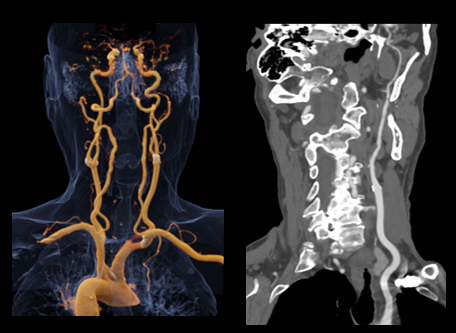

다음과 같은 검사가 가능합니다.

* 이해를 돕기 위한 이미지이며, 실제 촬영 시 이와 상이할 수 있습니다.